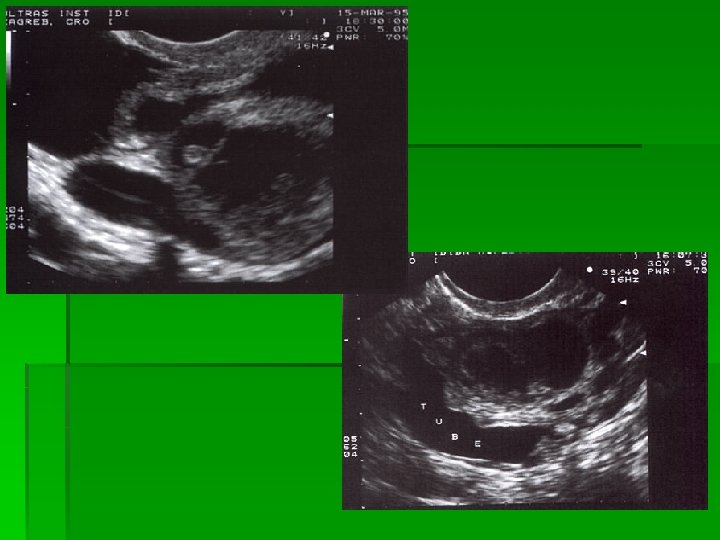

Corpus luteum Folikularna cista i pericistični protok

Ektopična trudnoća

PID